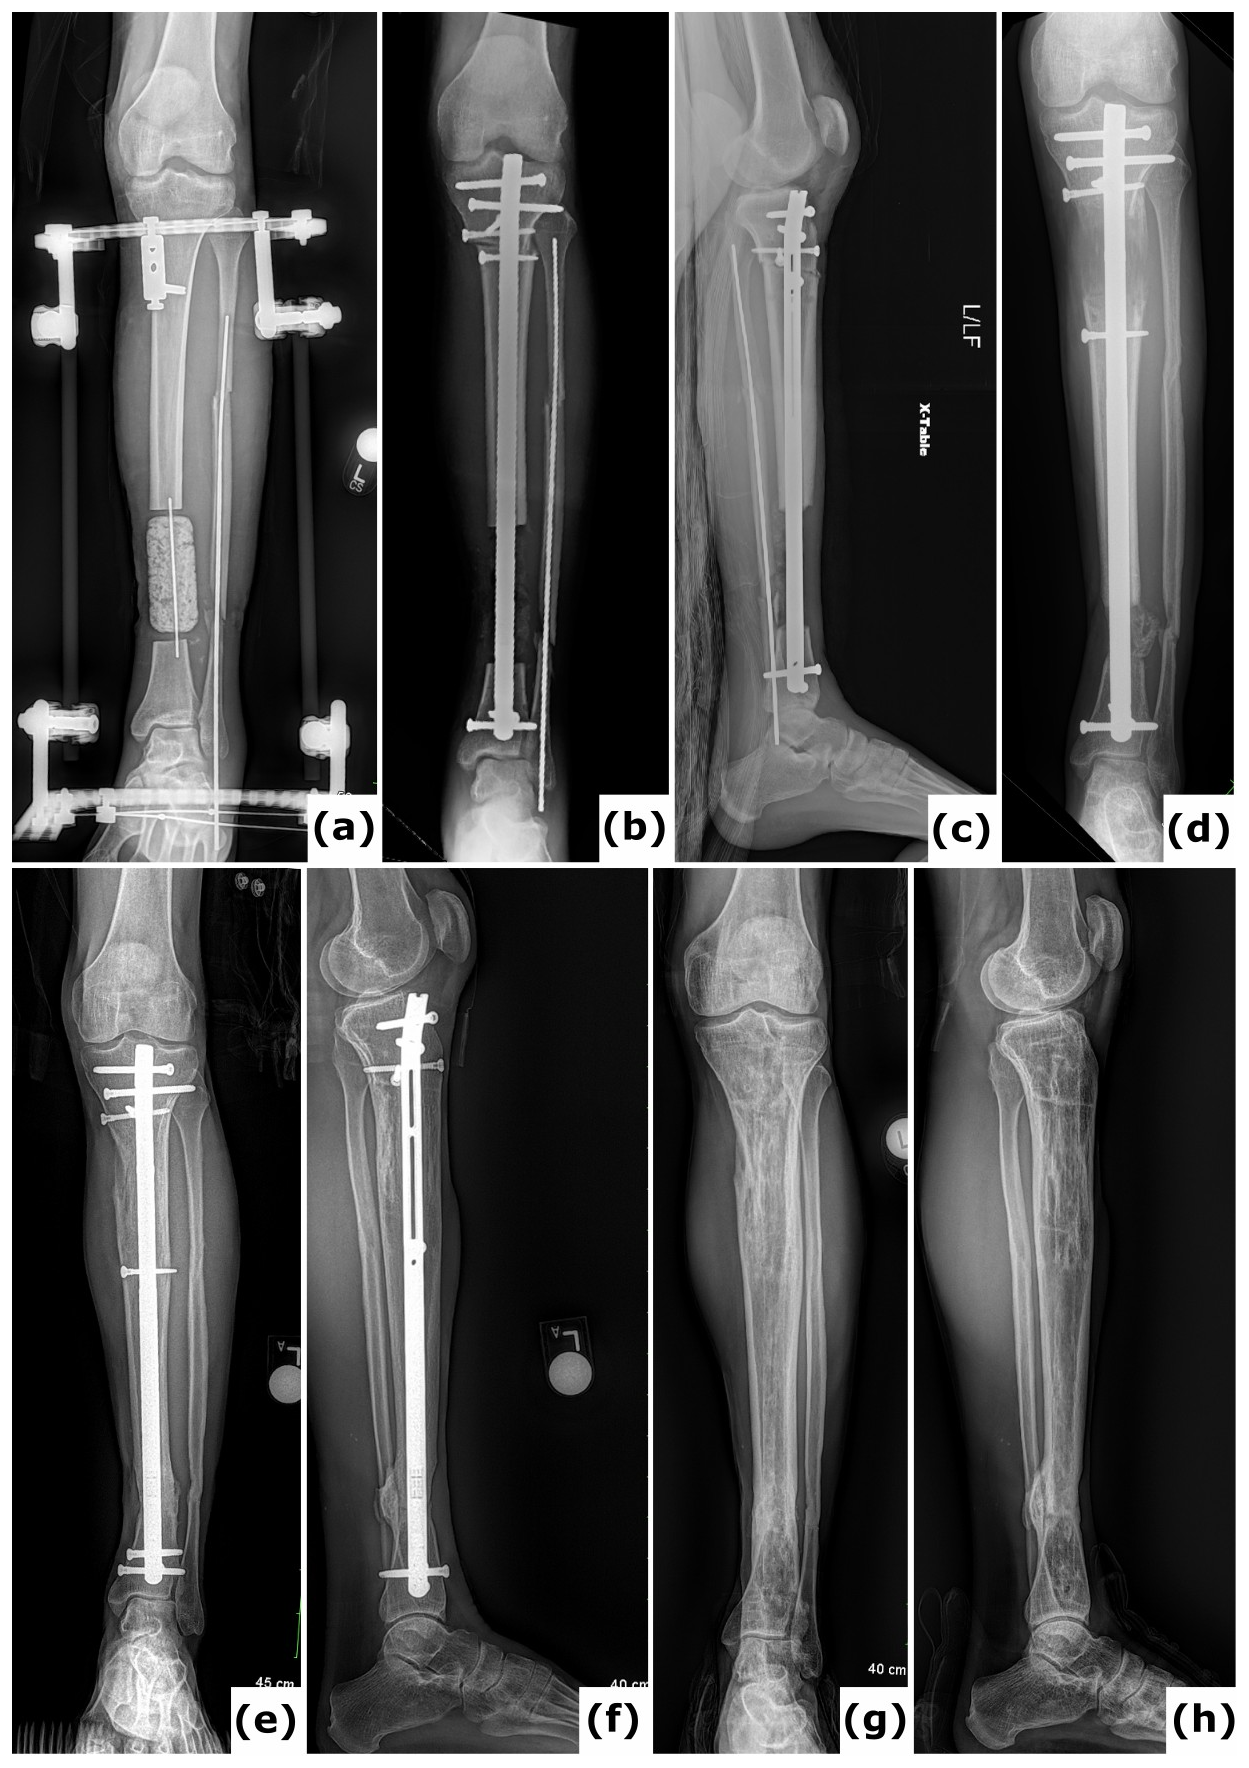

Figure 3Bone transport utilizing external fixation. A 51-year-old patient presented with a Gustilo-Anderson type II open fracture of the distal tibia and fibula. (a) Clinical presentation upon admission to the emergency department, illustrating the open fracture. (b–c) Computed tomography (CT) images obtained at the time of referral, 3 months after initial stabilization with a standard external fixator, reveal absence of bone healing and significant destruction of the tibiotalar joint. (d–e) Anteroposterior radiographs demonstrate ongoing bone transport using a conventional ring fixator. Intraoperative cultures were negative. Note: Due to severe peripheral artery disease, there was a high risk of amputation; consequently, the corticotomy was performed at a lower level than the standard metaphyseal site. (f–i) CT scans, as well as anteroposterior and lateral radiographs, confirm complete consolidation at all sites at 2 years post-procedure. (j) Clinical evaluation at 2 years showed no signs of infection, and the patient was able to ambulate independently.